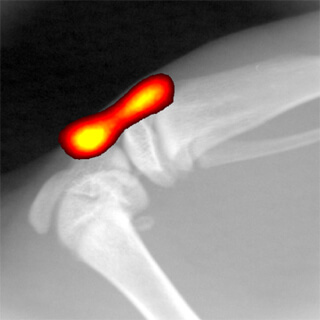

- Moduł obrazowania Rentgenowskiego

- Możliwość składania obrazów z fluorescencyjnych, luminescencyjnych i RTG.

- Moduł obrazowania Rentgenowskiego

- Możliwość składania obrazów z fluorescencyjnych, luminescencyjnych i RTG.

Aparat do przyżyciowego obrazowania zwierząt laboratoryjnych IVIS Lumina XRMS przeznaczony jest do badań dwuwymiarowych z zastosowaniem obrazowania luminescencyjnego, fluorescencyjnego oraz obrazowania promieniowania Cerenkova, a także RTG. Umożliwia to uzyskiwanie złożonych obrazów sygnałów fluorescencyjnych lub /i luminescencyjnych w kontekście obrazu RTG budowy anatomiczne zwierzęcia. Zaawansowana optyka, duży wybór filtrów wzbudzeniowych i emisyjnych, technologia Spectral Unmixing oraz wyposażenie dodatkowe takie jak dedykowany system anestezji gwarantują szerokie spektrum zastosowań aparatów IVIS Lumina XMRS zarówno w badaniach nad nowymi lekami, komórkami macierzystymi, rozwojem stanu zapalnego jak i w badaniach nad terapiami spersonalizowanymi. Standaryzacje badań gwarantuje możliwość absolutnej kalibracji zgodnej ze standardami NIST.